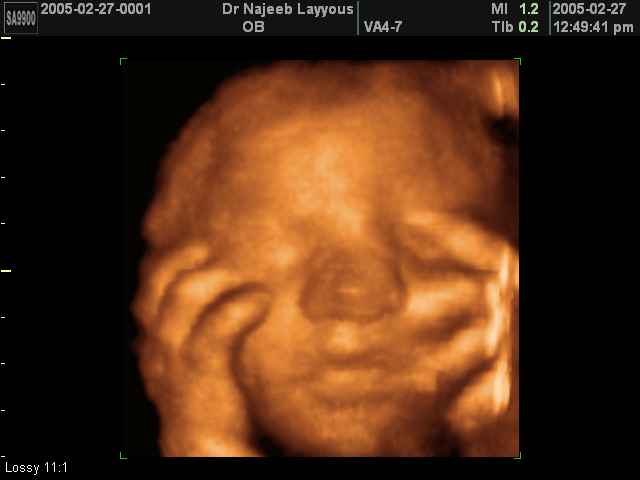

- تصرفات الجنين داخل الرحم

- صور لوجه الجنين في داخل الرحم

- صور لتصرفات الجنين داخل الرحم